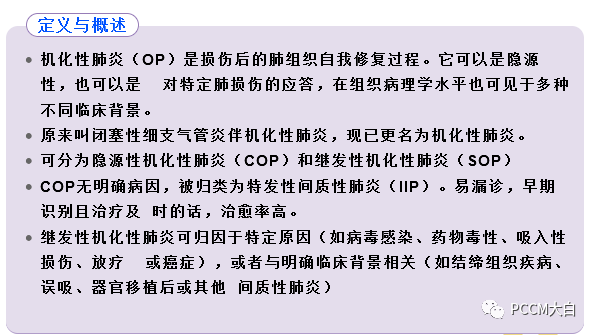

COP属于特发性间质性肺炎的一种,临床和放射学上与继发性机化性肺炎没有明显差别,但其病因目前尚不明确。COP发病率较低,男女相当,发病年龄可见于20~80岁,平均50~60岁。COP发病与吸烟无关,大多数患者不吸烟。

COP确切发病率和患病率尚不清楚。

年龄:患者确诊时的平均年龄为50~60岁(范围,17~95岁);儿童中很少有关于COP的报道。

性别:男性发病率略高于女性(男性发病率为52%)。

吸烟史:约54%的COP患者从未吸烟,46%既往或当前吸烟;在既往或当前吸烟者中,确诊时有不到15%的人自诉当前吸烟。

病理生理学

机化性肺炎的发病机制尚不清楚。从病理角度看,肺组织结构似乎未发生严重破坏。

COP是炎性和纤维增生过程,以肺泡内纤维增生为特征,经过免疫抑制或抗炎治疗后可逆(有时不可逆)。